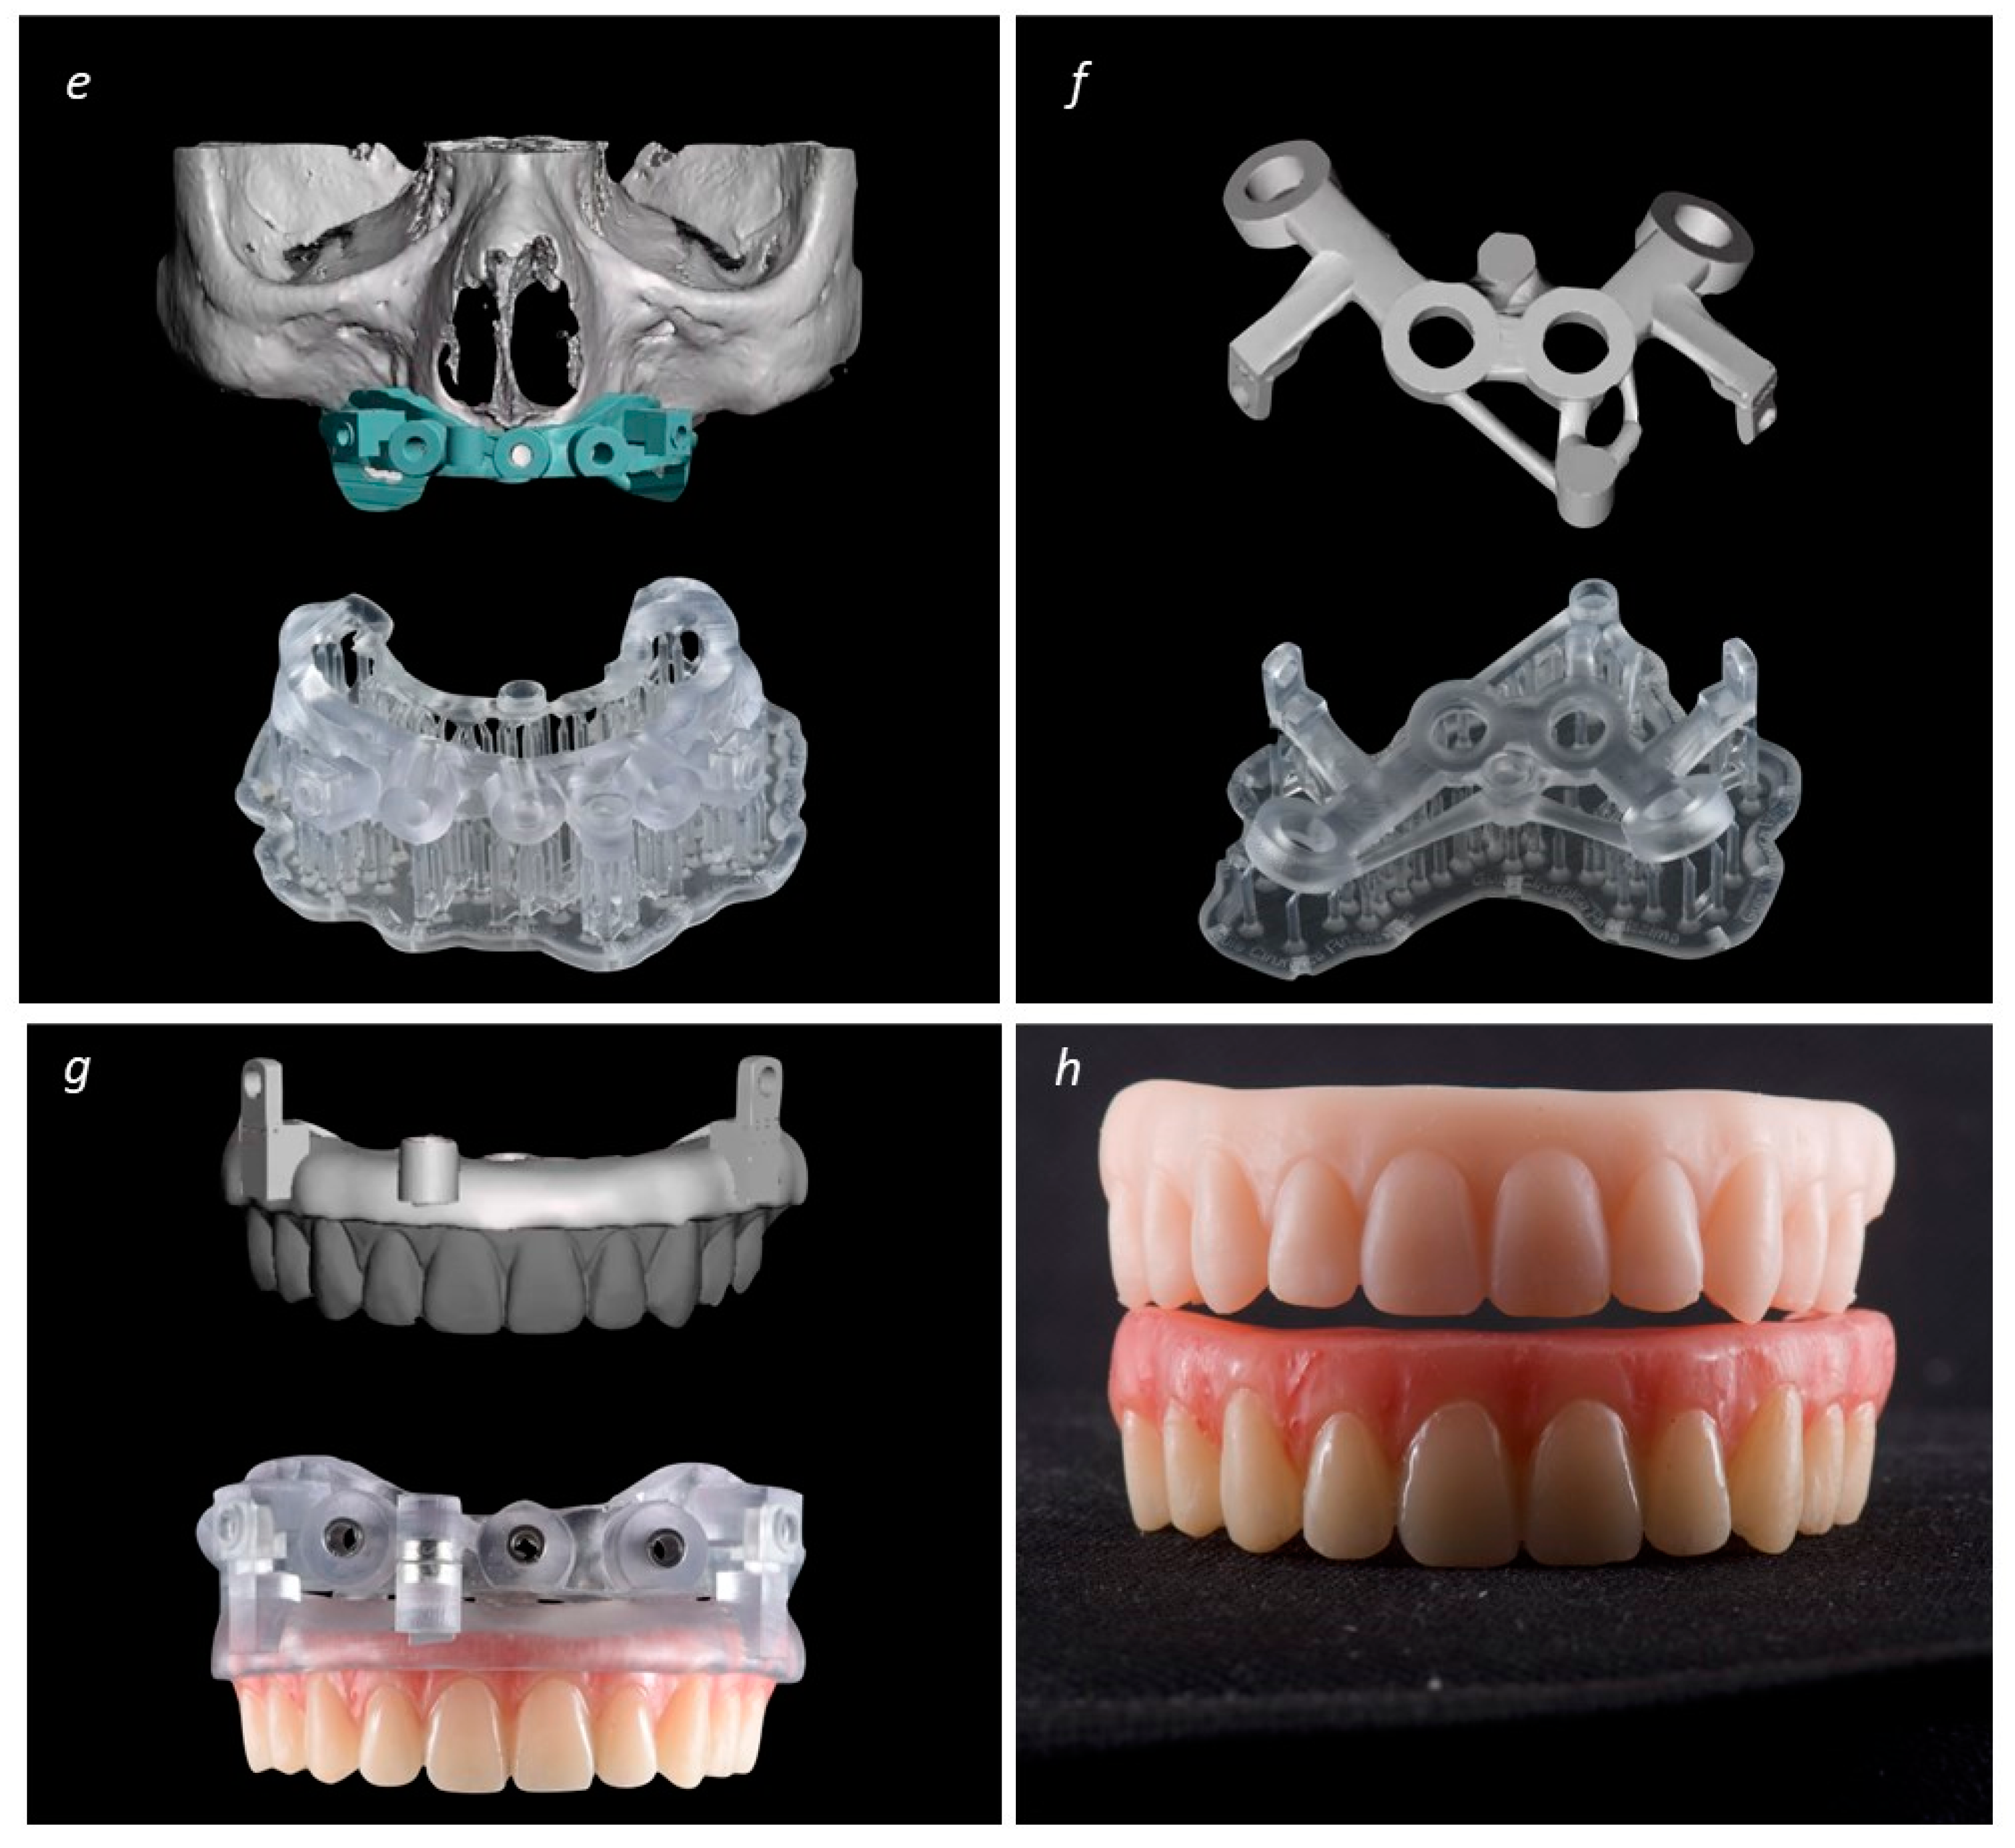

A New Full Digital Workflow for Fixed Prosthetic Rehabilitation of Full-Arch Edentulism Using the All-on-4 Concept

2. Materials and Methods

Description of the Technique

3. Results